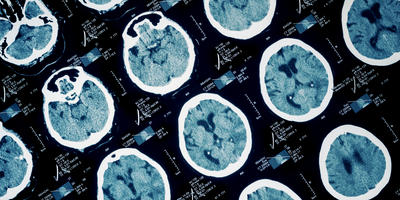

Study finds that glial fibrillary acidic protein levels in the blood can predict intracranial abnormalities on CT scans in patients with traumatic brain injury

Researchers demonstrate that neurofilament light chain in the blood can detect brain injury and predict recovery across all stages of traumatic brain injury